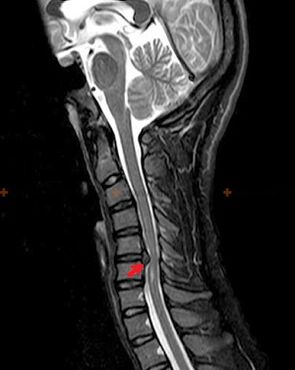

Диагностика и рентгенови признаци

Остеохондрозата е рентгенова диагноза, тъй като подробна клинична картина е налична само в момента на обостряне, докато промените в гръбначния стълб могат да настъпят при пълно субективно благополучие на човек. Без рентгеново изследване можем да говорим само за подозрение за остеохондроза, тъй като подобни симптоми могат да бъдат причинени от други заболявания (миозит, вертебрални неоплазми и други).

За диагностициране на остеохондрозата се използват следните методи за изследване: радиография (за предпочитане с функционални тестове), MSCT и MRI. Последното изследване е най-предпочитано поради факта, че позволява много ясно да се визуализира състоянието на междупрешленните структури.

Рентгеновите признаци на остеохондроза включват следните промени в гръбначния стълб:

- Намалена височина на междупрешленните дискове.

- Наличие на маргинални костни израстъци.

- Нарушаване на местоположението на прешлените един спрямо друг.

- Деформации на телата и дъгите на прешлените и др.

Наличието на описаните по-горе промени, както и промените в структурата на междупрешленния диск, открити чрез MSCT и MRI, служат като надеждни признаци, потвърждаващи наличието на остеохондроза.